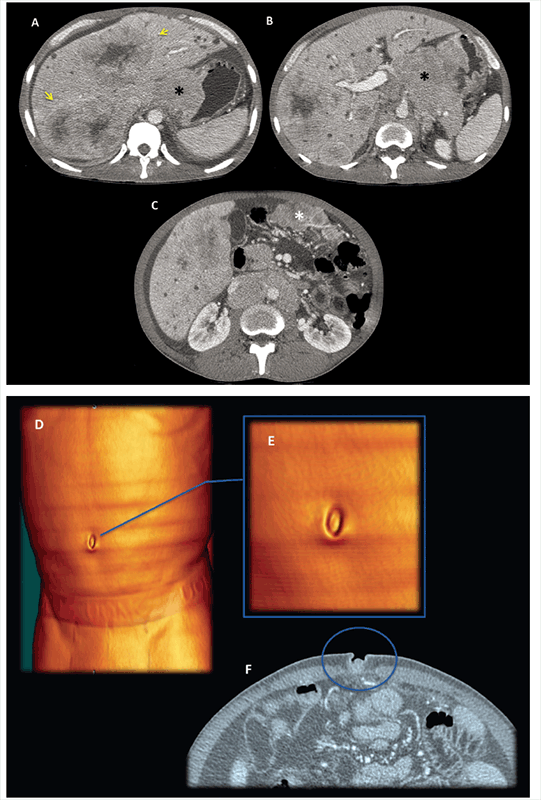

Contrast enhanced MDCT axial slices, in portal-venous phase: Images shows hipovascular liver metastasis and an extensive infiltrative retroperitoneal (*), vascular and peritoneal involvement. A SMJN can be appreciated in the umbilical area (E and F). Clinicians thought that they were leading with a non-complicated umbilical hernia. Left-sided portal hypertension syndrome consists in gastric and esophagus varices with patent portal vein and extensive splenic vein thrombosis secondary tumoral invasion and replacement of splenic vein (arrows). The peritoneal involvement denotes a small amount of loculated ascites and a slightly thickening of the peritoneum with some small nodular areas (arrow head). In this exceptional case, the omentum does not appear to have macroscopic involvement.

Contrast enhanced MDCT axial slices, in portal-venous phase: (A, B, C) Huge Gastric neoplastic mass with transmural involvement with non-defined borders that invades the omentum [white asterisk (*)], hepatoduodenal and gastrohepatic ligaments [black asterisk (*)]; hipovascular liver metastasis (yellow arrows). (D, E) Metastatic umbilical nodule SMJN (volume renderings, images, blue arrow and circle).